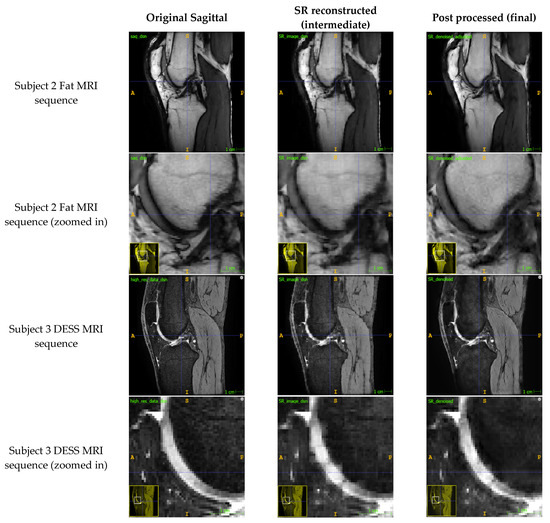

3. Results